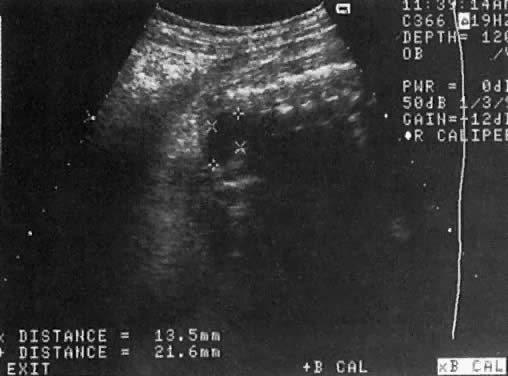

Renal Agenesis

The frequency of this condition is 1:4000 births, and the risk of recurrence is 3%.51 The etiology is variable and may include chromosomal or genetic disorders (recessive or dominant mode of inheritance). It may also be part of the VATER association: vertebral defects, anal atresia, tracheoesophageal fistula, and radial and renal dysplasia. The outcome of fetuses with renal agenesis is poor because of oligohydramnios and associated pulmonary hypoplasia.

Intravenous administration of furosemide (40 mg IV) has not been helpful in differentiating renal agenesis from severe intrauterine growth restriction. Further, because of associated oligohydramnios as well as an enlarged adrenal gland that mimics renal appearance, the diagnosis by gray scale ultrasound is difficult (sensitivity, 50%).51 In suspected cases, however, the use of color Doppler velocimetry may show absence of renal arteries in bilateral renal agenesis and only one renal artery in the unilateral form of this abnormality (Fig. 17).52

Fig. 17. A. Cross-section of fetal abdomen at level of kidneys (spine anterior, arrow) shows both kidneys. The areas on each side of the spine are filled with a uniform echopattern, and no kidneys are seen. B. Color Doppler of aorta in a fetus with renal agenesis fails to outline renal arteries.